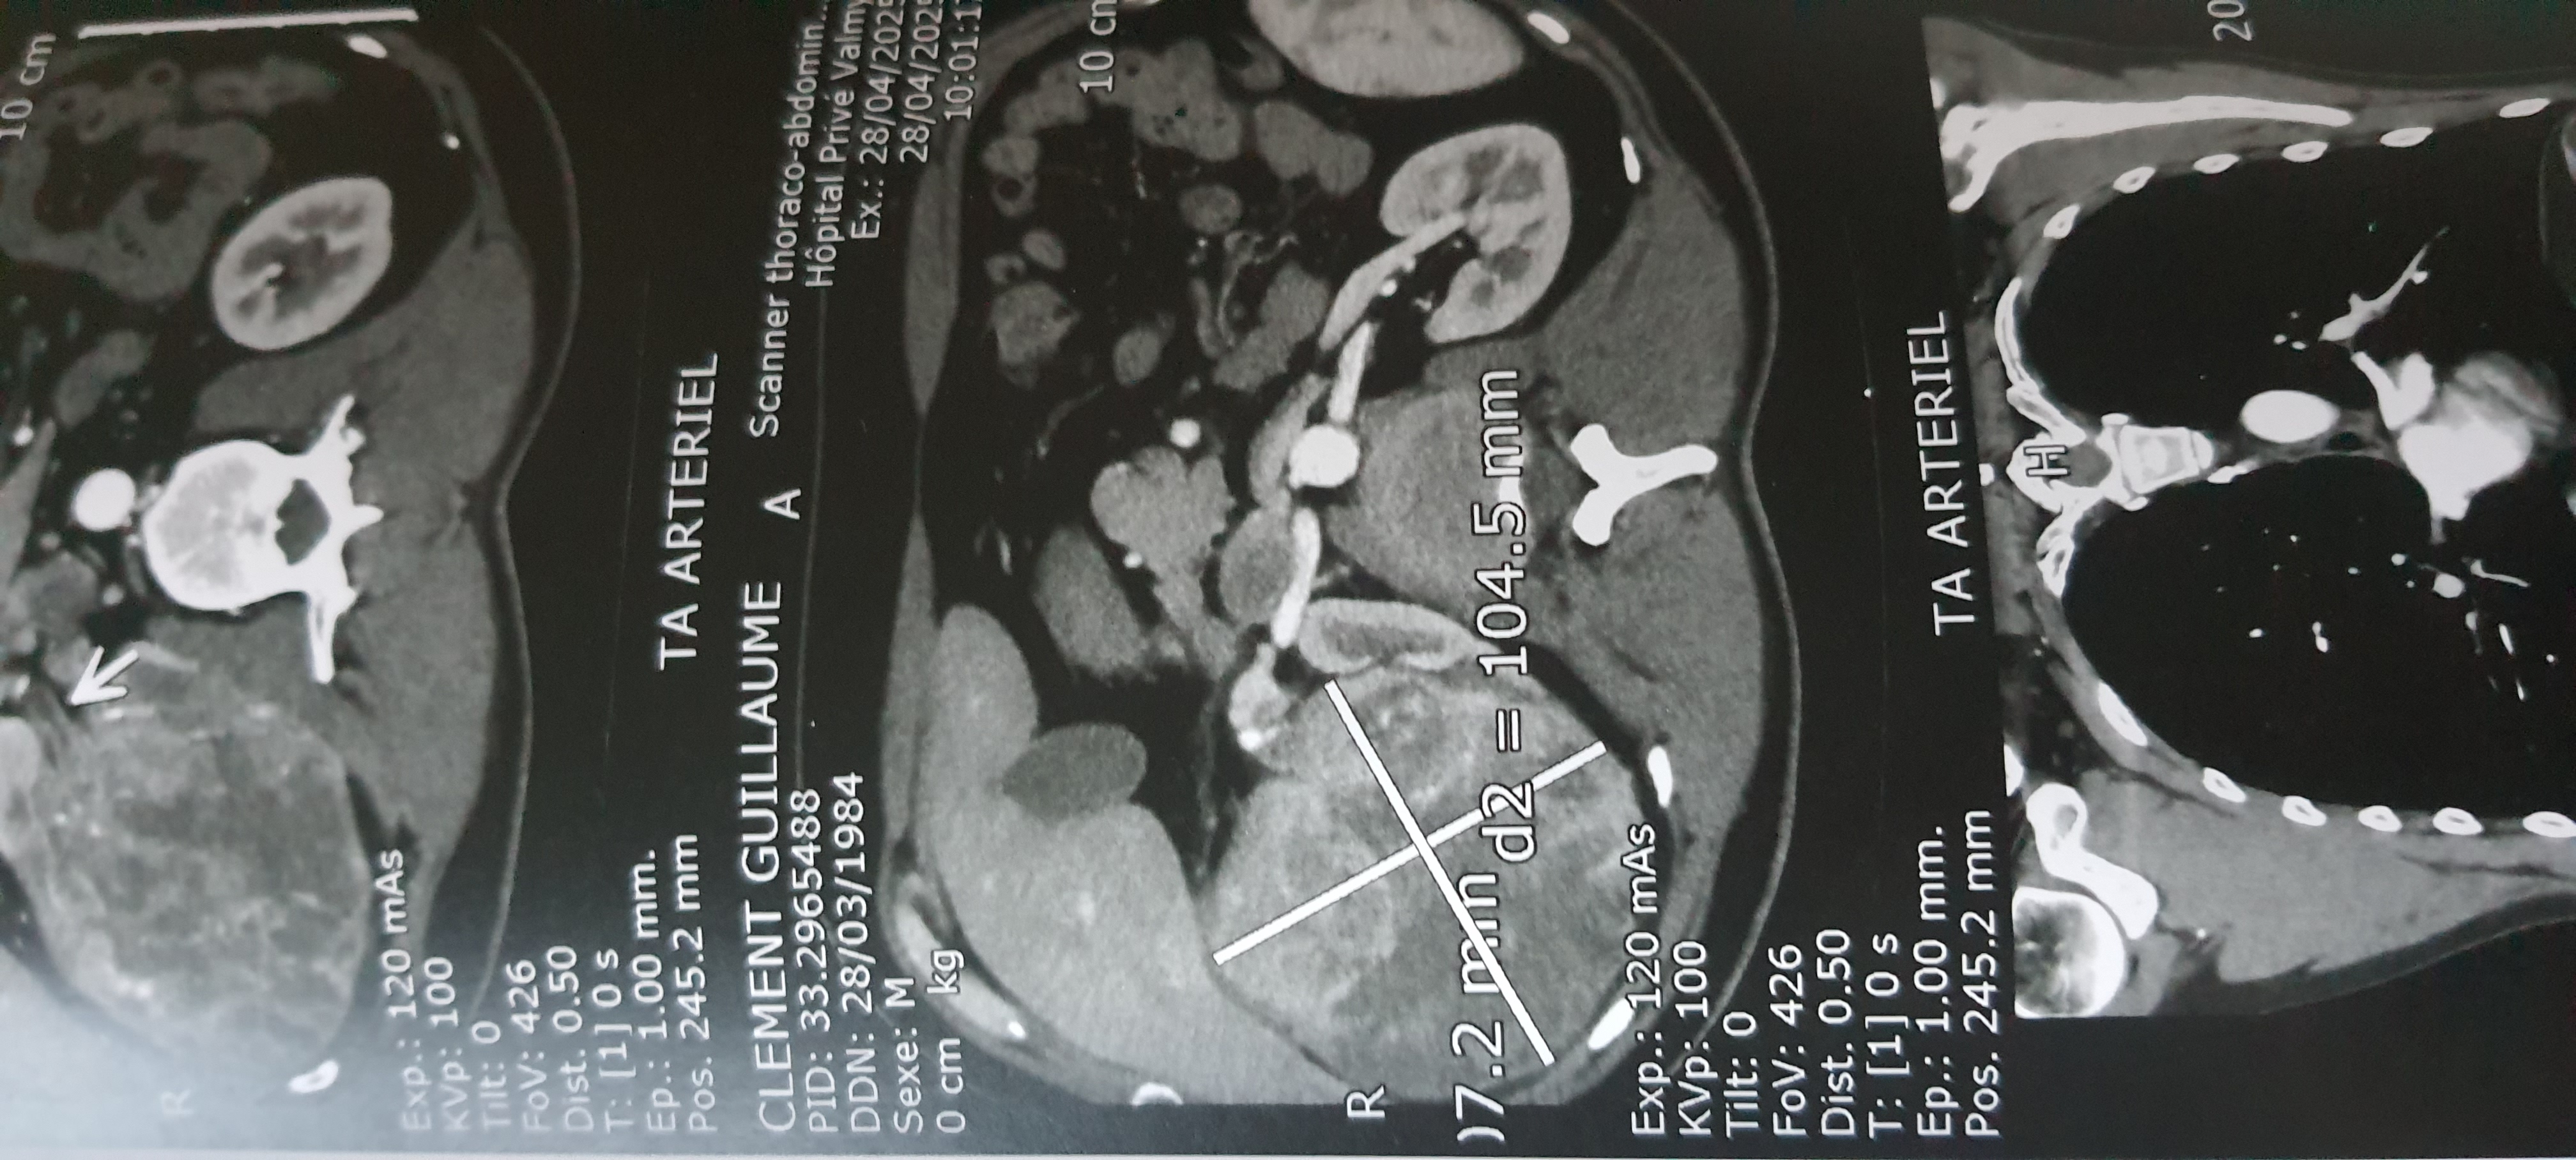

Suite à l’échographie, une masse d’environ 10 cm de diamètre a été détectée au niveau du rein, on m’a donc fait faire un scanner en urgence pour confirmer le diagnostic.

Une fois le scanner réalisé, on m’a dit qu’il faudra très certainement enlever le rein droit et consulter mon médecin traitant pour avoir un rendez-vous avec un urologue en urgence. Je pense que le but était que je comprenne que la situation était grave (pour être sûr que je m’en occupe). On ne m’a pas parlé de cancer explicitement, mais c’est bien de ça qu’on parle.

À gauche on voit le rein droit, qui aurait dû ressembler à l'autre, donc à une noix de cajou et pas à un melon

Pendant le scanner ils ont également vérifié s’il n’y avait pas de masses sur les poumons, et tout avait l’air bon de ce côté (les cancers du rein se propagent généralement à 75% aux poumons et à 20% au cerveau). Le cerveau n’a pas été vérifié, par contre.